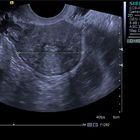

Гистероскопия — на данный момент самый безопасный и современный метод диагностики и лечения внутриматочных патологий, который обязан вытеснить рутинные травматичные методики. Гистероскопия матки - что это? Это введение гистероскопа, оснащенного видеокамерой в полость матки, визуализация структурных изменений полости матки, поверхности эндометрия и, при необходимости, возможность внутриматочных манипуляций под контролем гистероскопа.